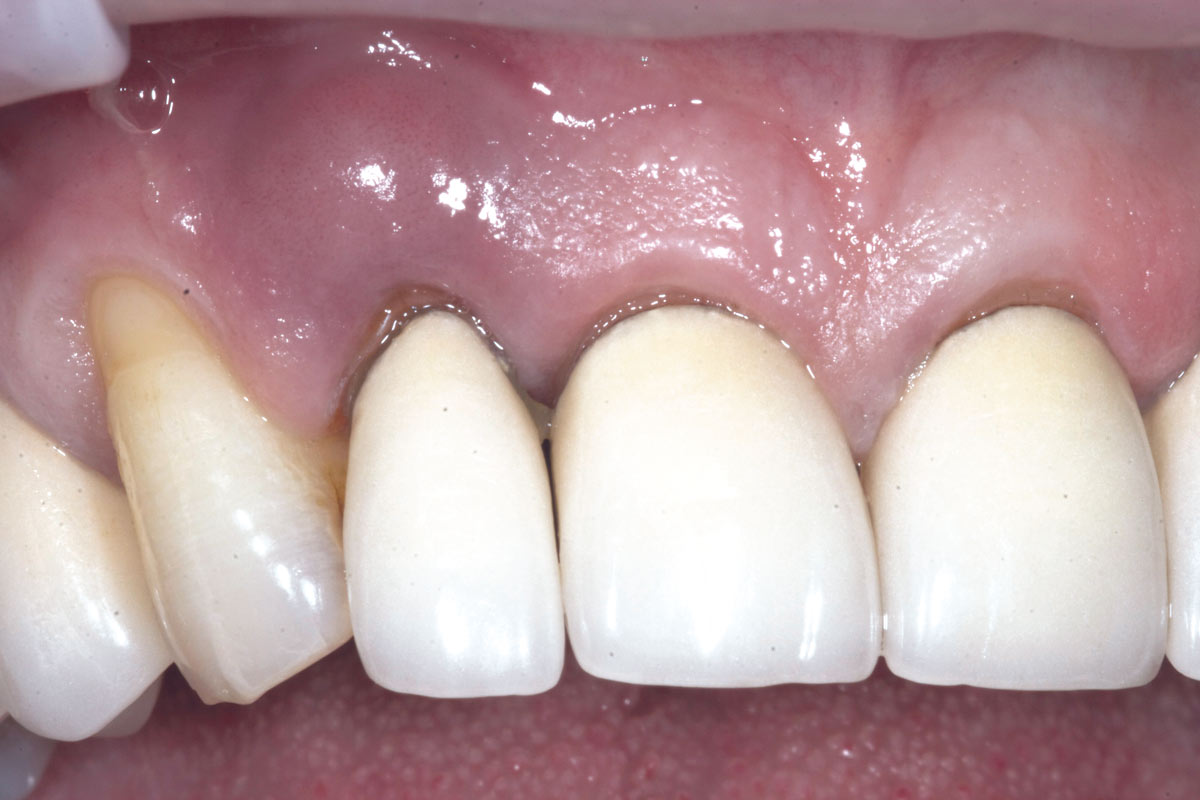

6/19 - Site without prosthetics showing sever buccal bone lossBone augementation with maxresorb® - Dr. R. Cutts